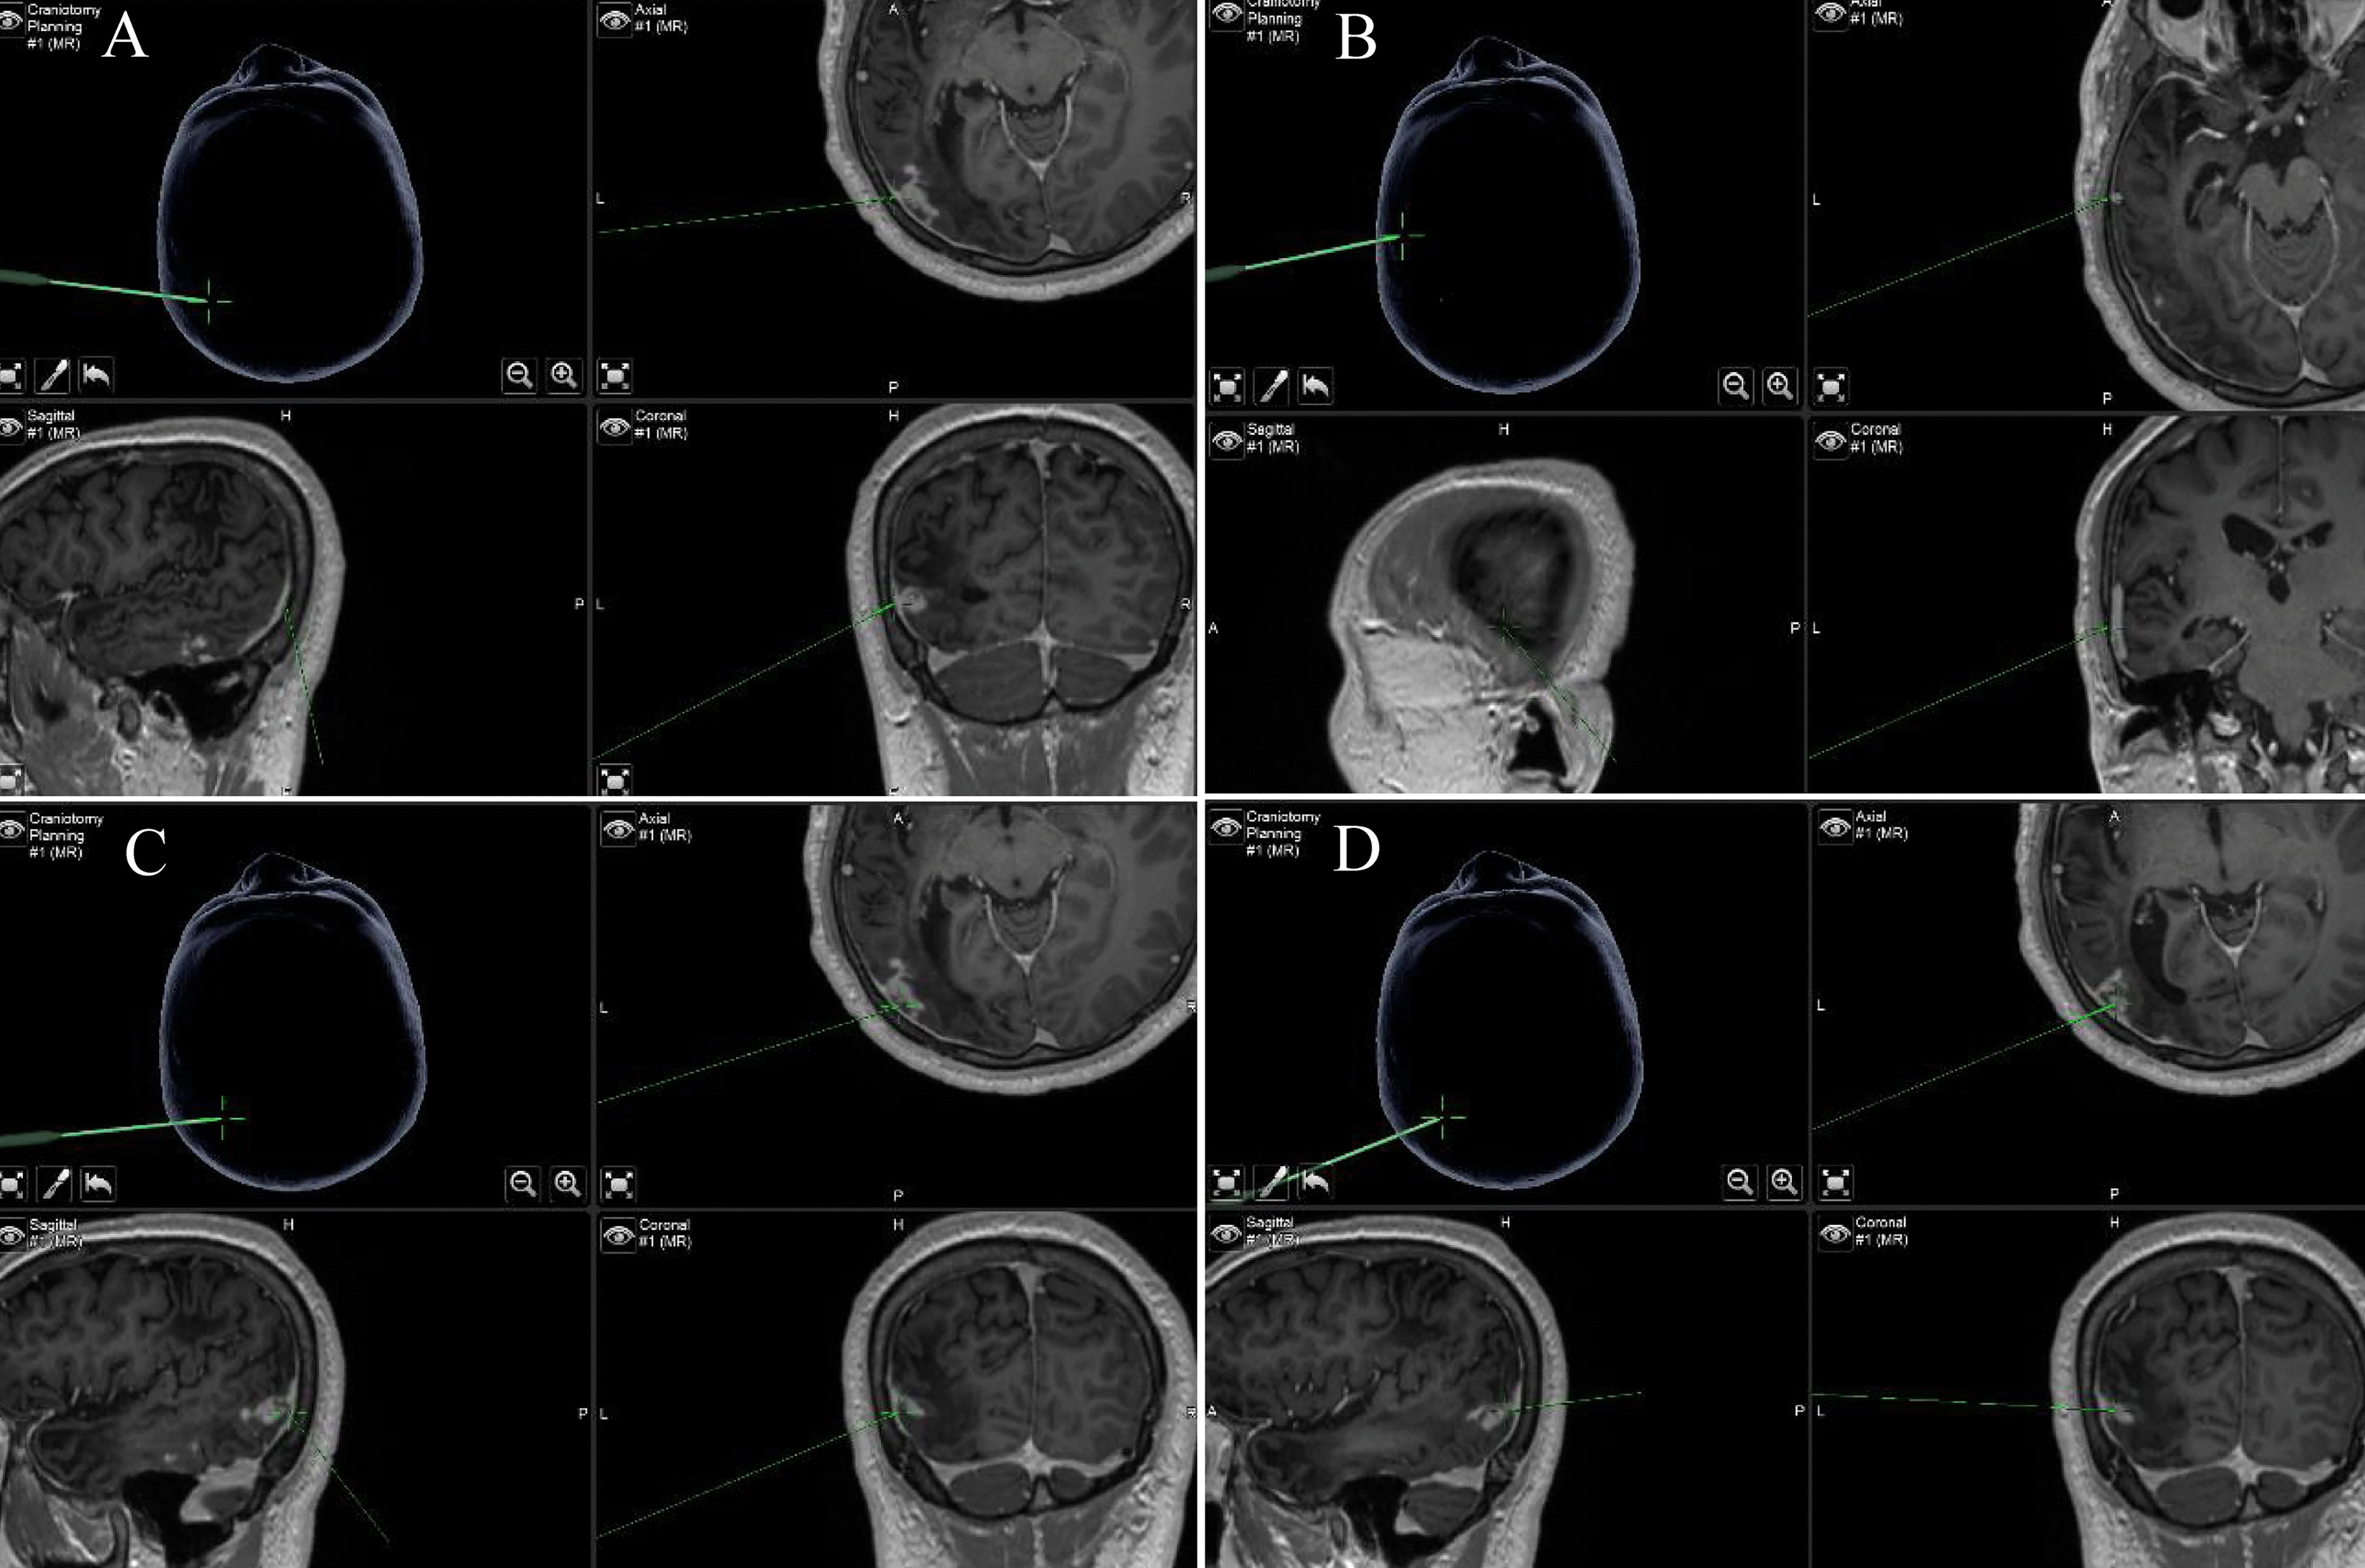

After successful general anesthesia, the surgical area of the patient was disinfected and draped, a left temporoparietal horseshoe-shaped incision 4–5 cm long was made, and the bone flap with a diameter of approximately 3 cm was removed with a milling cutter. MRI neuronavigation was used to locate multiple enhancement lesions in the temporal region (Fig. 2A–D), bordering the posterior border of the posterior lesions. Electrocoagulation incised the cortex to perform resection of the posterior lesions of the left temporal lobe. A live ivory-white parasite was removed from the surface of the lesions. The parasite was approximately 12 cm long and 0.5 cm wide, the head end was enlarged, the body was slender, and it moved actively like an amoeba in normal saline. The surgical area was then separated along the lesion, and a grayish-yellow, tough-textured area of edema around the lesion with edema was seen, and subtotal resection was performed. Suspicious parasites were found at the bottom of the inferior temporal gyrus with obvious enhancement, which were surrounded by granulomas, and the granulomas were excised. The lesions were taken for the anterior and posterior parts of the temporal lobe and sent for biopsy. Care was taken to avoid breaking the larvae and leaving any larval residue during the procedure. For illustrative purposes, we have also attached a video clip of the surgical procedure (Additional file 1: Video 1).

Fig. 2.

Neuronavigation and localization. (A–D) Neuronavigation combined with contrast-enhanced MRI to pinpoint lesions from sagittal, axial, and coronal, as indicated by green arrows